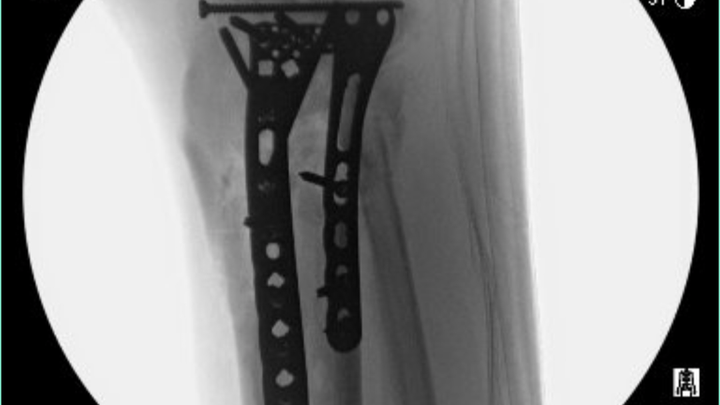

I'm Martin Rodriguez (Arnez to many). If you follow online, then you know the last four months have been difficult for me (to say the least). If you are new to me, allow me to share my story. I was hospitalized from May 24th, up to & including my rehabilitation stay. I am scheduled for release on September 28th. I had a terrible crash off my e-scooter. I ended up at the hospital with a broken leg (both tibia and fibula). The bones were so severely damaged one doctor told me they were obliterated below the knee. My journey has involved eight surgeries over nine weeks .